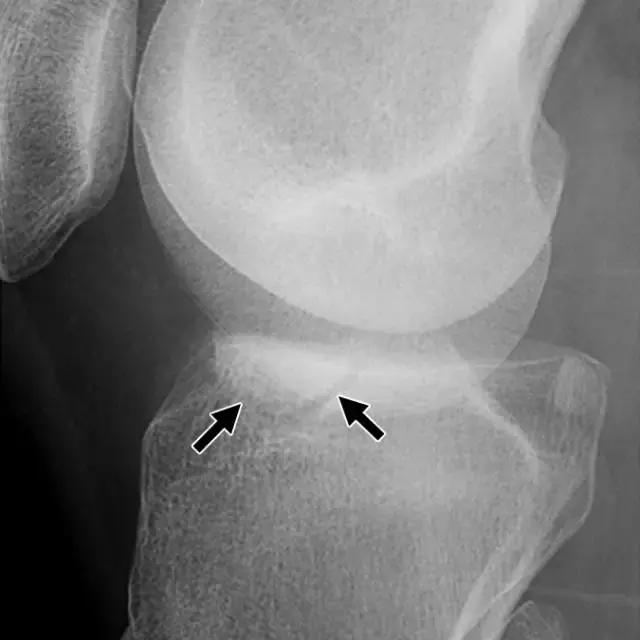

在放射照片上,Segond骨折显示为邻近近侧外侧胫骨平台的小骨片,并且在膝关节的前后放射照片上能很好的显示(图5A)。在MR图像上,由于相邻软组织中突出的异常信号强度,小的撕裂片段可能不像放射照片那样显着(图5B),但膝关节内更重要的损伤可以更好地显示。在75-100%的Segond骨折患者中发现ACL的撕裂,66-75%的病例中同时存在半月板损伤。

图5A -30岁的Segond骨折患者。A,膝关节前后位X线照片显示沿胫骨外侧平台的薄线状骨折片段(箭头)。

图5B骨折挫伤存在于股骨外侧髁上,前交叉韧带可以看到较低低信号,表明撕裂(箭头)。